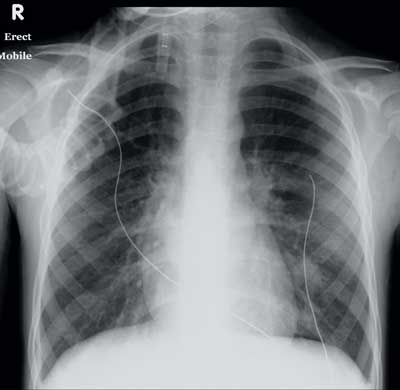

His respiratory status gradually improved and he was weaned off the nasal mask CPAP after 5 days, avoiding endotracheal intubation. He had clinically apparent subcutaneous emphysema, a small pneumomediastinum, but no pneumothoraces during his PICU stay. The chest radiograph before discharge from PICU (Box 1) showed increased perihilar opacities and left lower lobe infiltrates with resolution of the pneumomediastinum and subcutaneous emphysema. His improving spirometry measurements with treatment are shown in Box 2. He was discharged on Day 13 of admission with marked improvement in symptoms and an FEV1 (forced expiratory volume in 1 second) 66% of predicted.

1 Chest x-ray 3 days after admission to intensive care

Shows hyperinflated lung fields, perihilar inflammatory changes, emergence of an interstitial infiltrate in the left lower lobe and a small right-sided pleural effusion.